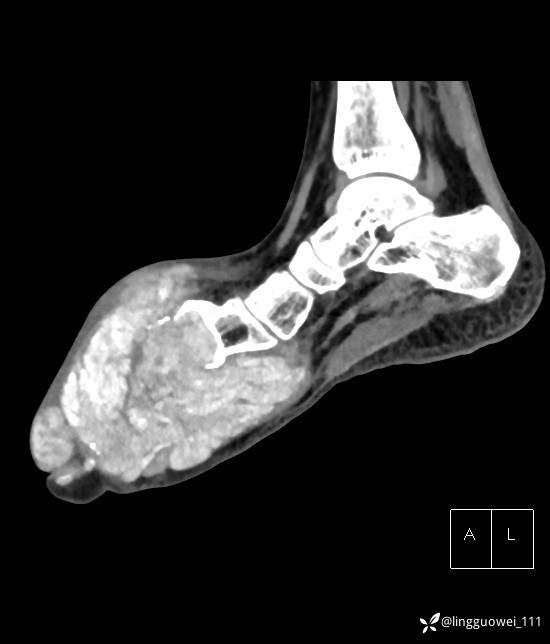

28岁男性,工作中遇到的足部最大的肿块,已补充临床资料。

28岁男性,足部肿块逐渐增大2年。能找到病因吗?

患者于2年余前高嘌呤饮食及大量饮酒后出现全身多处关节痛风石,以右足第一跖趾关节和右手为显,局部红肿热痛反复发作,自行口服药物后可缓解(药物可疑为强的松、双氯芬酸钠等,具体不详)。2年来右足痛风石明显增大,约10cm*5cm*15cm,局部红肿发热,3天前患者再次大量饮酒后痛风石顶部破溃,可见4cm*3cm皮损,较多白色豆渣样分泌物流出,为求进一步治疗来诊,门诊诊断为“右足痛风石破溃伴感染”, 收住院拟手术治疗,患者起病以来,无发热,精神佳、胃纳好、睡眠佳,大小便正常。

专科检查:右足外观畸形,足背部可见巨大痛风石形成,痛风石大小约10cm*5cm*15cm,局部皮肤红肿发热,痛风石顶部破溃,可见4cm*3cm皮损及白色豆渣样分泌物流出;痛风石界限清,质偏硬,局部触及波动感,无压痛,移动度差。右足踇趾及第2趾被痛风石压迫,关节活动受限。肢端血运、感觉无异常。 右手稍肿胀,2-5指背侧可见多发痛风石形成,最大者约花生米大小,皮肤完整未破溃,痛风石界限清,质偏硬,局部触及波动感,无压痛,移动度差。